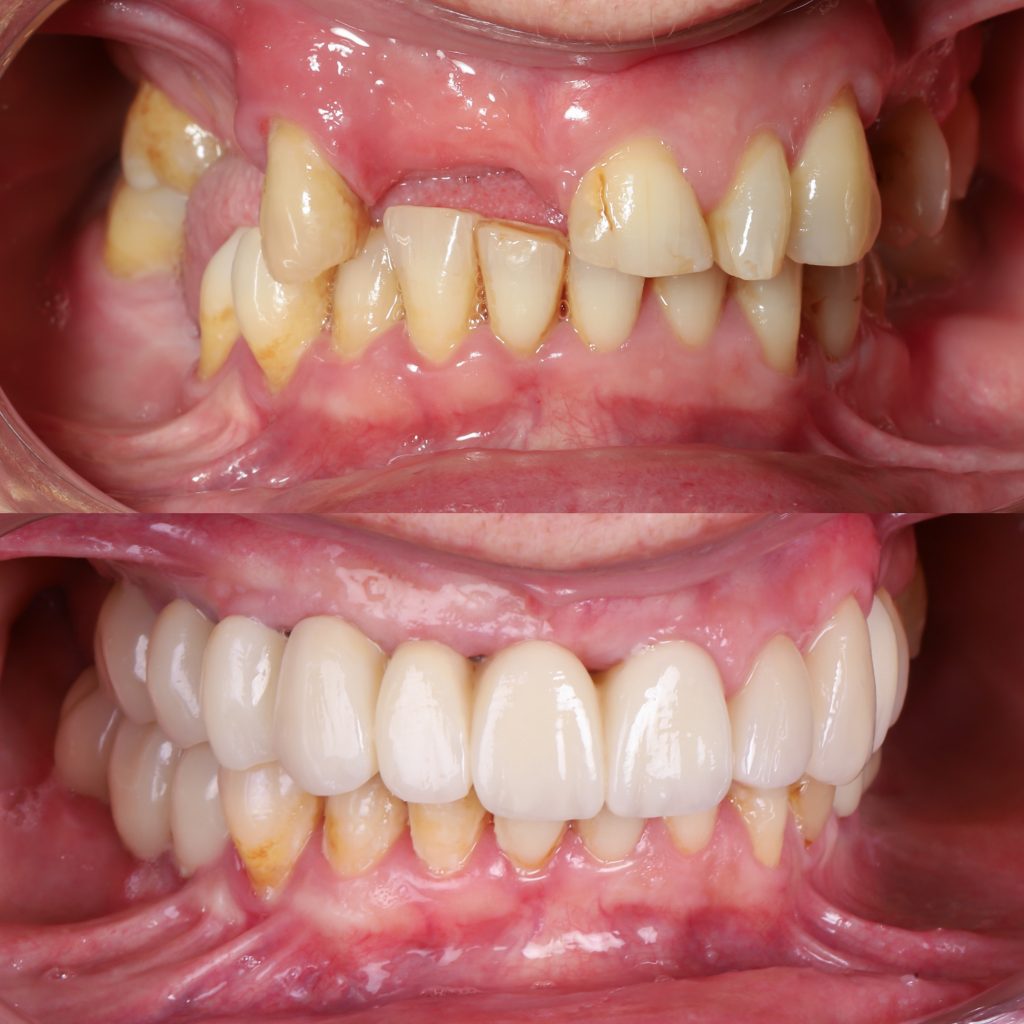

Historias de transformación

Si alguna vez te han dicho que tu caso no tiene solución, en Alejandro Prieto Dental desafiamos los límites de la odontología para ofrecerte la respuesta que estabas buscando.

Visualizar la transformación

Los cambios de imagen de la sonrisa favorecen mejoras cuidadosas y matizadas, para obtener resultados naturales que garanticen el equilibrio general y la armonía facial.